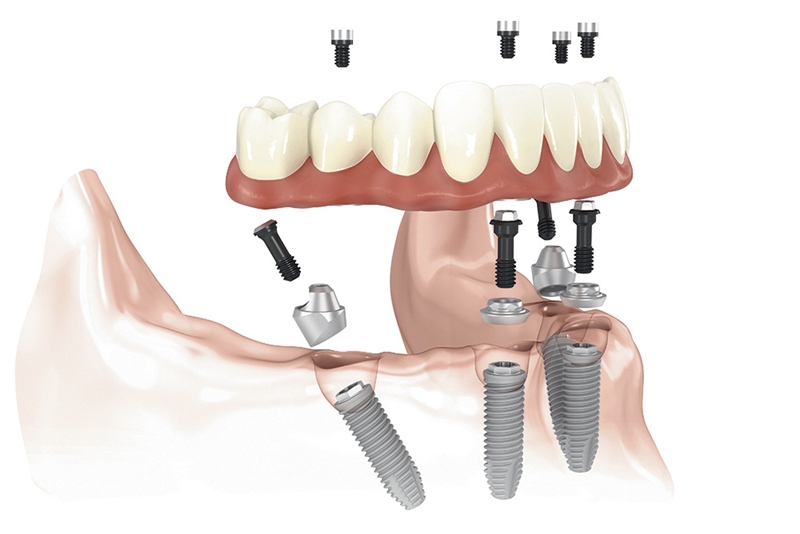

„A fogpótlásra szolgáló klasszikus megoldással, vagyis a kivehető protézissel szemben az implantáció jóval stabilabb, ezzel együtt tartósabb megoldást nyújt. Teljes foghiány esetén pedig egyértelműen az All-on-4 eljárás az egyik legjobb opció, amit a páciensek választhatnak.” A módszer lényege, hogy a teljes fogsor rögzítéséhez mindössze négy implantátum, speciális dőlésszögben történő beültetése szükséges, melyek teljes stabilitást biztosítanak. „Amellett, hogy az All-on-4 technológia gyorsabb és költséghatékonyabb választás, segítségével részben, vagy akár teljesen elkerülhető a hosszabb regenerációt igénylő csontpótlás is.”

Az All-on-4 fogsor módszere azért is arat átütő sikert, mert a hagyományos megközelítéssel szemben itt mindössze 4 implantátum behelyezése szükséges, ezáltal olcsóbb, és nem utolsó sorban az új fogsor elkészítése sokkal gyorsabb, hiszen az implantátumok behelyezése után 1-2 napon belül elkészül az ideiglenes pótlás, ami használatra kész. “Az ideiglenes pótlás azonnal terhelhető, az implantátumok gyógyulása pedig nagyjából 4-6 hónapot vesz igénybe, ami után elkészülhet a végleges pótlás.”